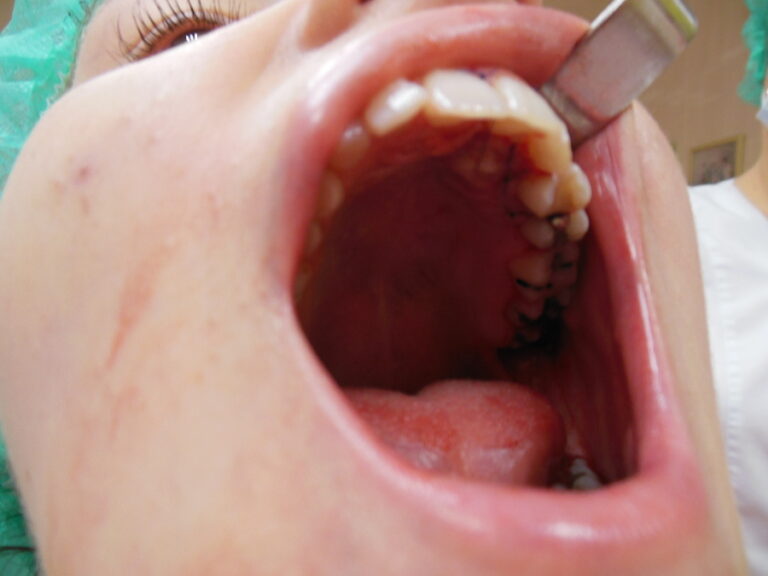

Ortodoncja CBCT

Leczenie chirurgiczno-ortodontyczne wad zębowych z zastosowaniem tomografii spiralnej CBCT w naszej klinice.